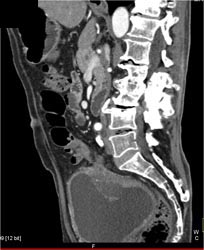

Diagnosis

Bladder Cancer